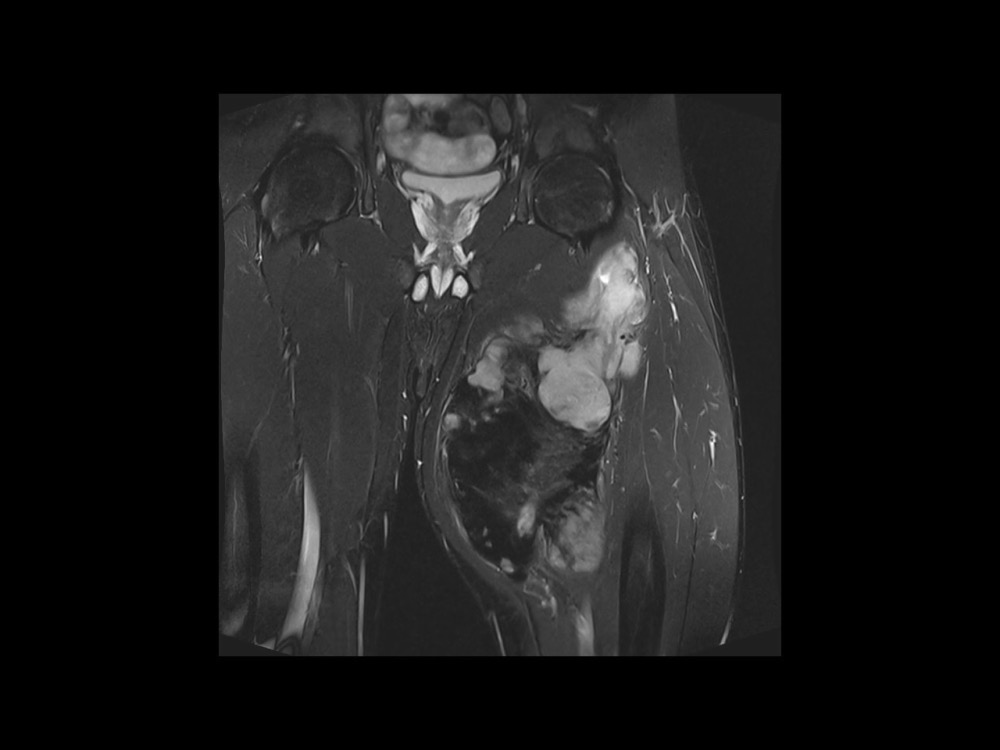

Moalla / Mihoubi-Bouvier / Drapé 18/05/2022